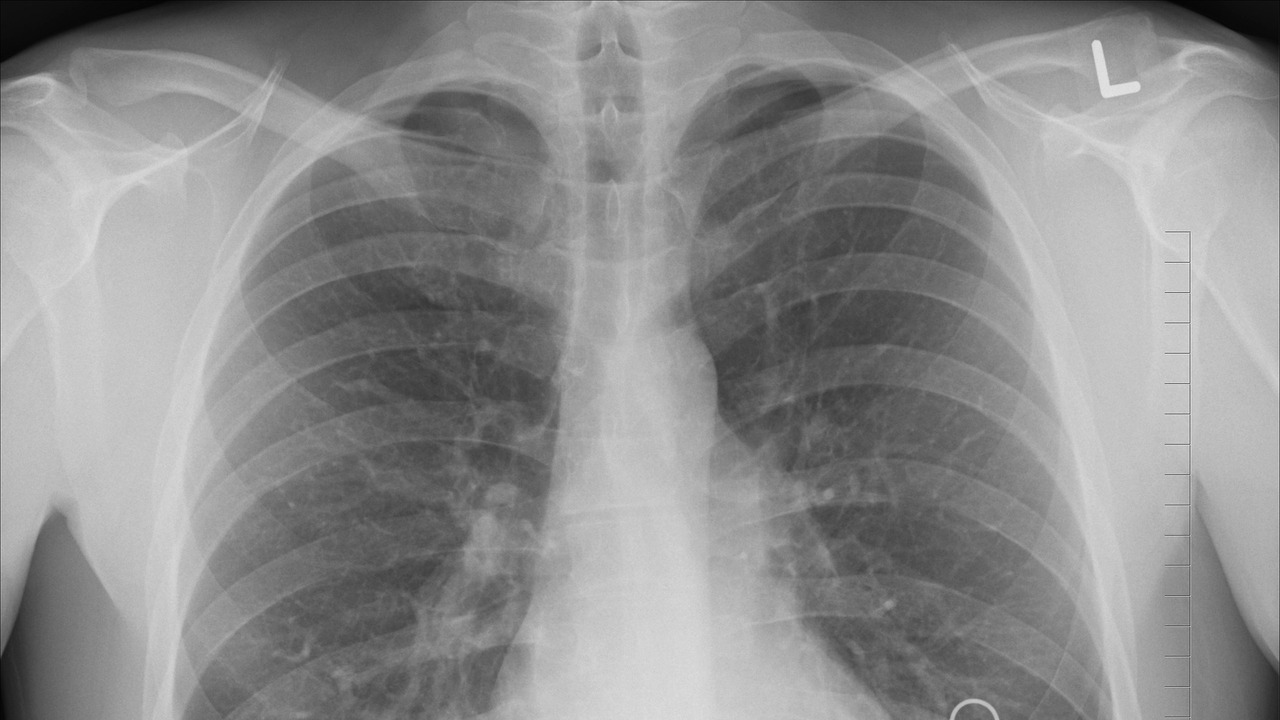

Фото с сайта pixabay.com